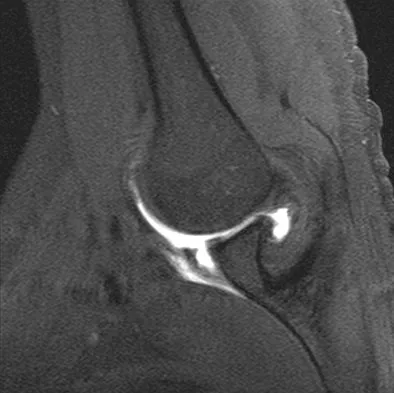

A healthy 16-year-old boy has had increasing pain in the right knee for the past 3 months. Examination reveals warmth and swelling around the distal femur. Radiographs and an MRI scan are shown in Figures 51a through 51c, and a biopsy specimen is shown in Figure 51d. What is the most likely diagnosis?

Explanation